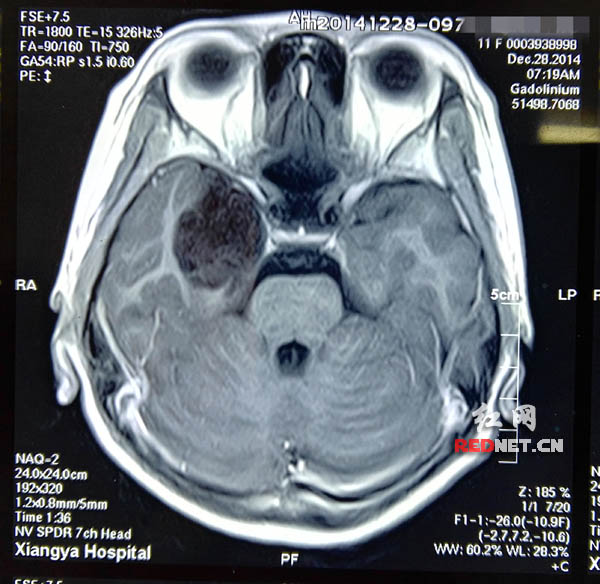

12岁女孩偷窃成瘾 原是颅底肿瘤压迫致人格改变

图片尺寸600x584